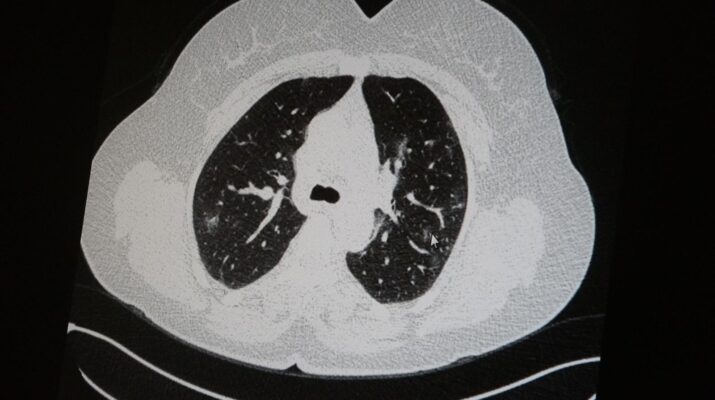

Elazığ’da öksürük, halsizlik, yorgunluk ve çabuk yorulma gibi şikayetlerle hastaneye başvuran ve koronavirüs tespit edilen 2 genç hastadan aşısız olanının tomografi sonuçlarında virüsün akciğerlerde zatürreye sebebiyet verdiği görüldü. Aynı şekilde aşı olup koronavirüs hastalığına yakalanan bir başka genç hastanın bilgisayarlı akciğer tomografisinde akciğerinde herhangi bir sorunun olmadığı belirlendi.

Medical Park Elazığ Hastanesi Göğüs Hastalıkları Uzmanı Dr. Cebrail Azar, geçtiğimiz yıla oranla yoğun bakımda yatan hastaların yaş ortalamasının 65’ten 35’lere kadar düştüğüne dikkat çekti. Genç olduğu halde aşı olmayanlarda hastalığın ağır seyrettiğini ifade eden Uzm. Dr. Azar, “Ben gencim, benim bağışıklık sistemim kuvvetli” diyen genç bir hastanın akciğerlerinde ciddi lekelenmelerin olduğunu ve koronavirüs zatürresi olduğunu gördüklerini belitti. Uzm. Dr. Azar, aynı şekilde aşı olup koronavirüs hastalığına yakalanan bir başka genç hastanın akciğer tomografisinde akciğerde herhangi bir sorunun olmadığını ve hastanın durumunun iyi olduğunu gözlemlediklerini kaydetti. Uzm. Dr. Azar, sürekli şahit oldukları “Keşke biz aşı olsaydık” sözünü bir daha duymamak için herkesi aşı olmaya davet etti.